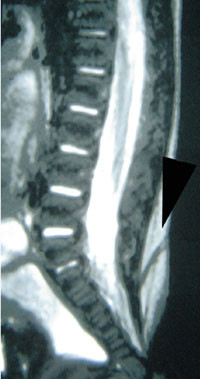

Ved diastematomyeli er ryggmargen spaltet i sagittalplanet, slik at man på ett eller flere nivåer har to separate ryggmarger (1) (fig 6). De to ryggmargene kan ha hver sin durasekk (type 1), og tilstanden skyldes da en beinspore som peker posteriort fra bakre del av corpus på ryggvirvelen og ”spalter” ryggmargen. Alternativt finner man to ryggmarger innenfor samme durasekk (type 2), og et fibrøst drag eller en beinspore skiller ryggmargene (8). Felles for begge typer diastematomyeli er høy risiko for tjoret ryggmarg. Diastematomyeli er ofte ledsaget av en fortykket filum terminale og lumbosakrale hårdusker (1). Hos omkring halvparten finner man også en ledsagende syringomyeli (1).

Skoliose forekommer med varierende hyppighet ved de forskjellige formene for okkult spinal dysrafisme. Skoliose finnes relativt hyppig ved diastematomyeli, mens det f.eks. er sjeldent ved kort filum terminale. Videre er det kjent at tjoret ryggmarg uansett årsak er en viktig etiologisk faktor (15). Pasienter som utredes for progredierende skoliose, må undersøkes med spinal MR for å utelukke underliggende ryggmargsmisdannelse, særlig ettersom man har holdepunkter for at nevrokirurgisk løsning av en tjoret ryggmarg kan bremse eller stoppe skolioseutvikling (15).